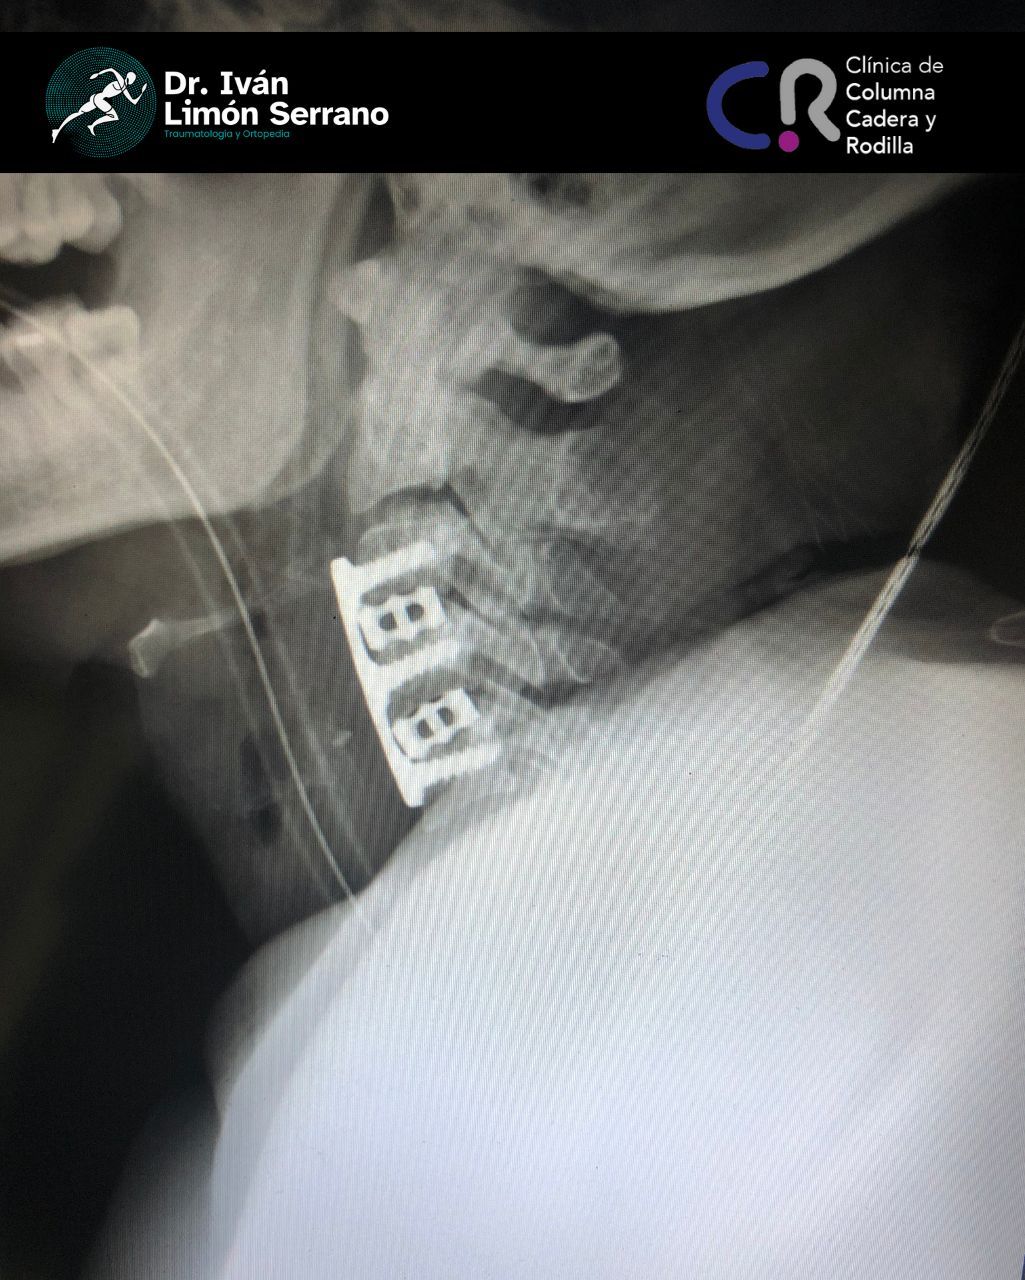

• Cirugía de columna

• Cirugía columna

Hernia de disco

Es una lesión que afecta a las estructuras de la columna vertebral, específicamente discos intervertebrales los cuales son estructuras blandas de consistencia gelatinosa cuya función es actuar como un amortiguador que absorbe el impacto y permite el movimiento de las vértebras. En ocasiones como ocurre durante los esfuerzos y los movimientos bruscos el disco se somete a una gran presión con lo que su anillo fibroso se desgarra, bien sea parcial o totalmente; este desgarro origina un trayecto por donde el material gelatinoso sale de su sitio originándose una hernia discal.